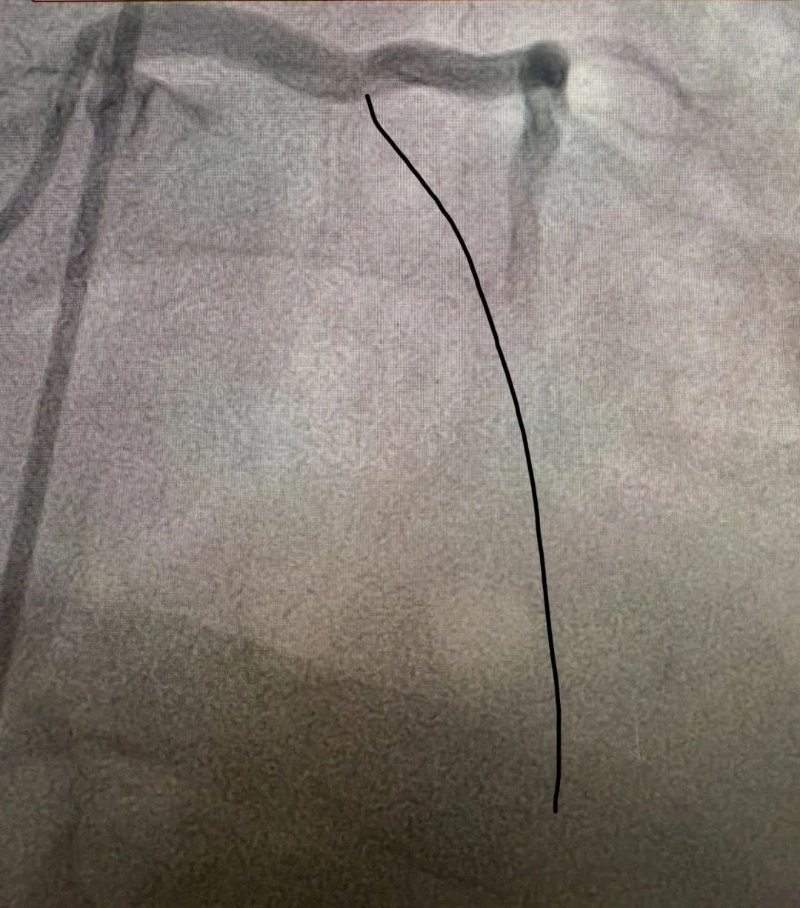

心脏恢复跳动意味着有了手术机会,患者被迅速送入介入室。介入室技师和护士早已准备就绪,惠州市中心人民医院中文博彩平台分院麻醉科医生也已到位。手术由温灵武和文轶医生共同完成。造影显示,患者前降支开口处完全闭塞,医生迅速开通闭塞血管并植入支架一枚,术后血流恢复良好。从患者进入介入室到血管开通,仅用时20余分钟。

手术后血流恢复